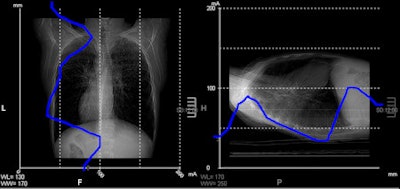

Screenshot from CT console depicting chest scout view. The horizontal axis represents the dose, the vertical axis slice positions -- the blue line indicating the dose requirements on a particular position at a given noise level. It can be perceived that on the lower chest part dose requirements approximate less than 25 mA.In an unrelated article published online 29 December 2011 in the European Journal of Radiology, Dr. Padma Rao, a consultant pediatric radiologist at the Royal Children's Hospital in Melbourne, Australia, and colleagues provide advice about when and how to perform pediatric head CT exams. They recommend the use of a MRI exam if it is clinically feasible, but proceed to describe common indications when a CT exam is indicated.